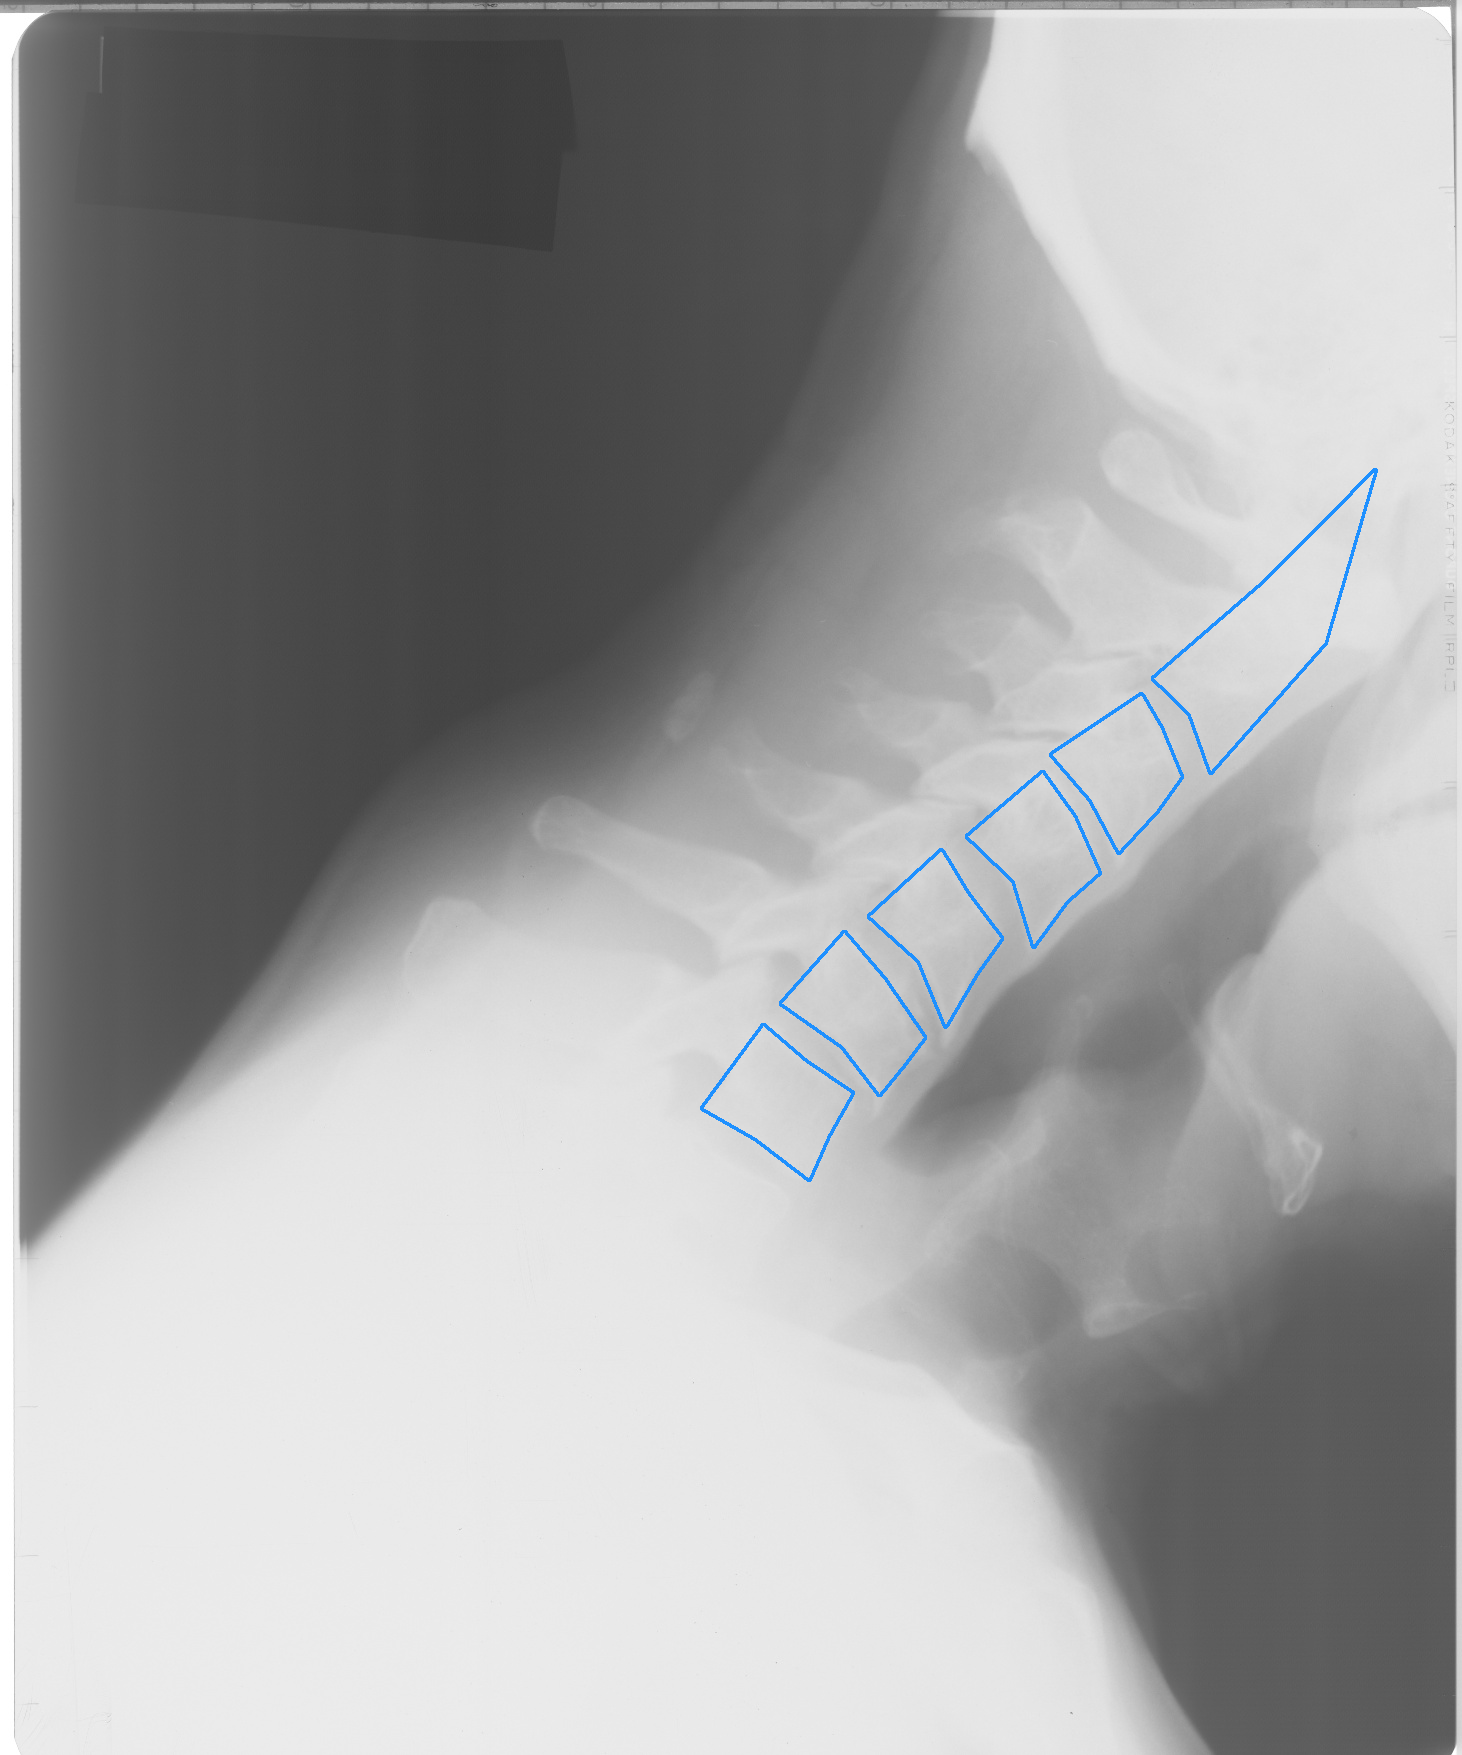

Fig. 1: Example X-ray images from NHANES II (left, center) and CSXA (right) datasets, with annotated vertebrae outlined in blue.

Our method was developed and tested using two publicly available datasets: the Second National Health and Nutrition Examination Survey (NHANES II) [10] and the Cervical Spine X-ray Atlas (CSXA) [11]. See Fig. 1 for example images.

CSXA comprises 4,963 cervical spine X-rays, each with complete annotations marking all four corners of the C3-C7 vertebrae. Unlike NHANES II, CSXA images are of higher quality and exhibit consistent FOV. We used a subset of 600 samples from this dataset, split evenly between training, testing and validation.

(b) Poor-quality ground truth masks (e.g. squares) from CSXA dataset

Fig. 3: Examples of limitations related to each dataset, showcasing specific challenges encountered in spine X-ray segmentation

Tab 2 demonstrates that the robustness of our pipeline, achieving an average DSC of over 0.93 across most vertebra levels, with some levels even surpassing 0.96. Achieving such high DSCs is challenging due to inherent ambiguities in defining the exact boundaries within X-ray images. Furthermore, since each ground truth mask is constructed as a polygon from just seven landmark vertices, and so it may not perfectly represent the true shape of the corresponding vertebra (see Fig. 3(b)).

While all CSXA X-ray images are of high quality and have consistent FOV, we observed a similar overall DSC to the NHANES II dataset, along with a decrease in the average DSC for the located vertebrae. We believe that this decrease is not due to a decline in segmentation performance but rather a consequence of the ground truth masks, which inadequately evaluate segmentation quality. Since the dataset only provides annotations for the vertebra corners, each mask is represented as a simple quadrilateral that does not accurately reflect the true shape of the underlying vertebrae. This limitation is evident in Fig.3(b). Consequently, the DSCs calculated from these masks do not truly represent the quality of our predictions.